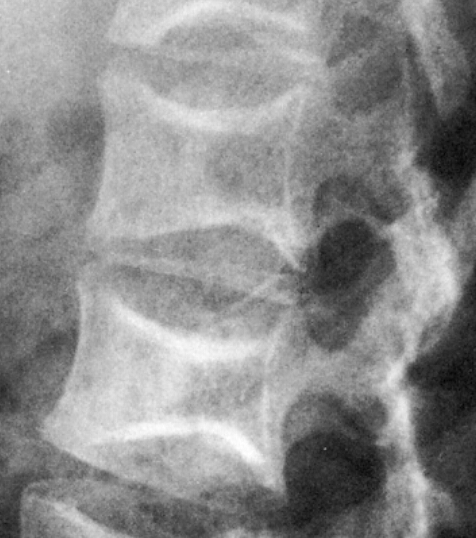

What is the radiographic feature?

codfish deformity